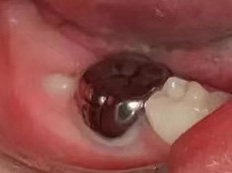

龋齿充填后注意事项

6、后牙龋坏缺损较大或龋坏位置不容易充填固位,患牙充填体反复脱落,建议行预成冠修复;

7、龋齿充填后应保持良好的口腔卫生习惯, 3-6个月定期复查。